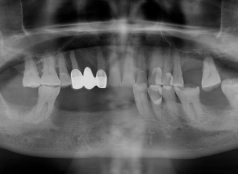

• Tình trạng răng trước đây:Mất nhiều răng ở 2 hàm.

• Bác sĩ chỉ định:Cấy ghép 8 trụ Implant.

• Implant sử dụng:Implant Nobel Biocare Thụy Điển.

• Răng sứ sử dụng:Răng sứ Titan Mỹ.

• Cấy ghép 8 trụ Implant

Chú Thi Văn Quang đến nha khoa I-DENT để khôi phục răng mất bằng phương pháp Implant. Trong suốt hành trình từ bước đầu thăm khám đến nhổ răng hư và cuối cùng là tiến hành trồng 8 trụ Implant, chú Quang cảm thấy rất êm đềm, không hề đau chút nào cả.

Giờ đây khi đã thoát nỗi ám ảnh, chán chường với hàm tháo lắp lỏng lẻo, yếu ớt, chú Quang đã có răng Implant chắc khỏe, có thể ăn uống thoải mái, không còn phải e dè, lo lắng khi ăn nhai, tận hưởng trọn vẹn hương vị cuộc sống của tuổi trung niên.